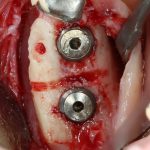

Я зафиксировал костный блок практически без адаптации на несколько винтов. Обрати внимание, что винты находятся в зоне, где не планируется установка имплантатов. Фиксация должна быть надежной, поскольку мне еще предстояла подготовка лунок для имплантатов. Трех винтов для этого вполне достаточно.

Дальнейшая адаптация костного блока свелась к сглаживанию острых краев. После чего я приступил к подготовке лунок и установке имплантатов.

Установка имплантатов.

Напомню, что для этой работы я выбрал субкрестальные имплантаты Ankylos C/X. Они прекрасно сочетаются с любым методом остеопластики.

Глянем на то, что получилось: